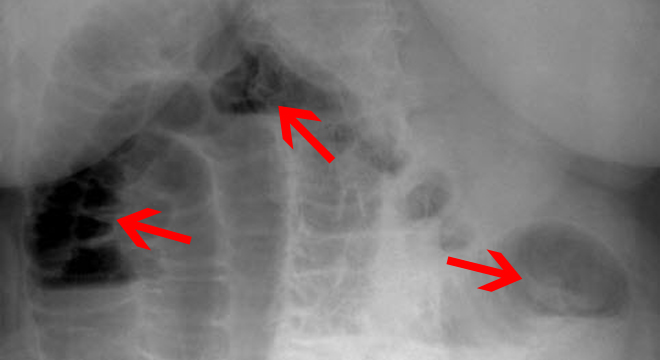

• Röntgenaufnahmen des Bauchraums (Abdomens), evtl. mit Kontrastmittel